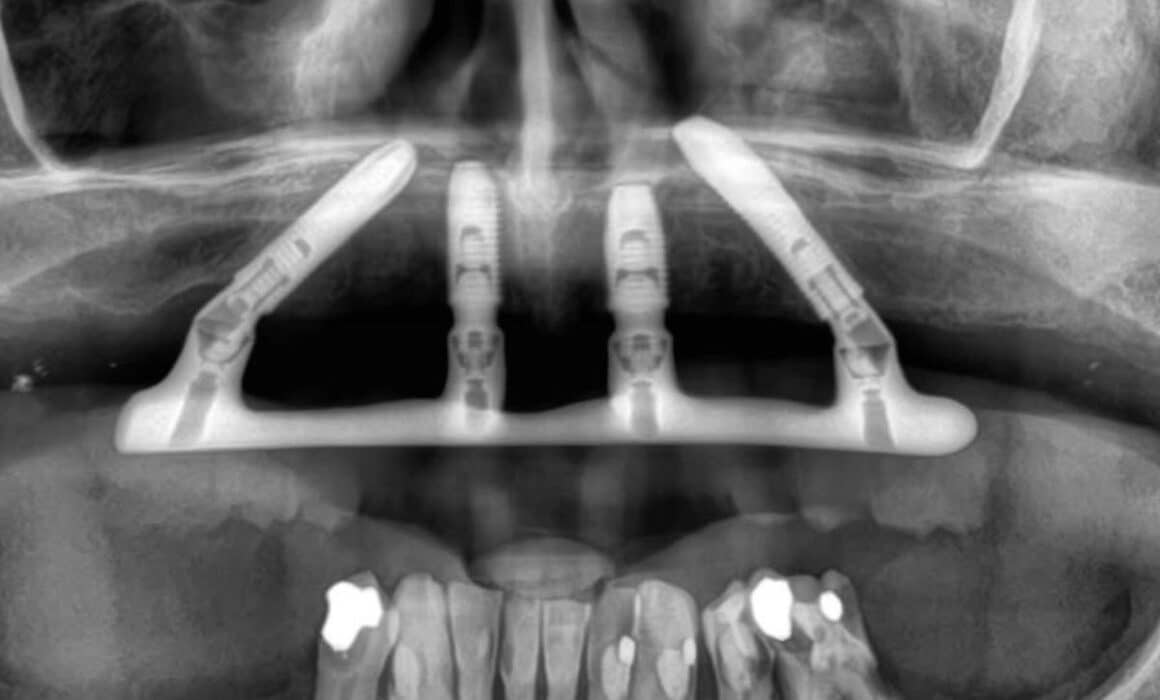

Unlike standard dental implants, that involve two surgeries and multiple appointments over several months, the All-on-4® protocol is to fit your new teeth to dental implants within 3–5 days of surgery. Our dentist will outline the process in your personal treatment plan, which is as follows.

2. Implant surgery

Our experienced dental surgeon will place all of your implants during a single surgery. If you need any other procedures, such as tooth removal or bone grafting, these can normally be done in the same procedure. We’ll then take an impression of your implants that our dental technician will use to custom design your bridge and place temporary healing caps over the top of each one.

Within 5 days of your implant surgery, our dentist will attach your permanent bridge and check that you can speak and bite comfortably. We’ll advise you about caring for your new teeth and provide you with a water flosser to clean under the bridge.